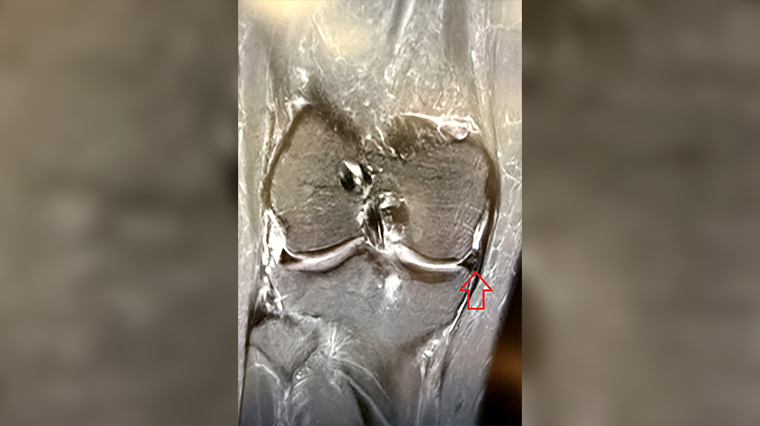

▲手術後半年,可見移植的半月軟骨。(圖/台北慈濟醫院提供)

林坤輝醫師表示,有關移植方法,是利用內視鏡在膝蓋開1個2公分的小洞及2至3個小於1公分的傷口,把關節內的碎片清除後,將骨骼捐贈者的半月軟骨置入患處,再將其與周圍組織縫合固定,以恢復膝關節功能。由於是將骨骼捐贈者的半月軟骨移植至病人體內,一般需要3個月的時間才能夠恢復既有彈性,因此病人在期間需要配戴護膝及使用拐杖分擔膝蓋壓力,待半年後功能接近穩定,即可嘗試輕度、輕量運動。